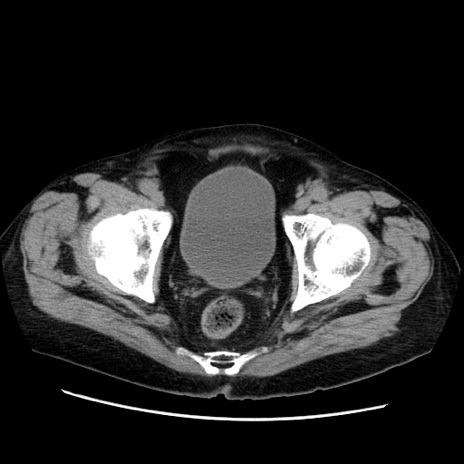

症例21(横断像)

【症例】70歳代男性

【主訴】腹痛

【現病歴】肝硬変・肝細胞癌にてかかりつけの方。約9時間前に食後より腹痛出現。症状が徐々に増悪し、嘔吐出現したため来院。

【既往歴】肝硬変、肝細胞癌(RFA、TACE後)

【身体所見】意識清明、表情苦悶様、BT 36℃、BP 129/78mmHg、P 88bpm、SpO2 97%(RA)、右上腹部から心窩部にかけて圧痛あり、反跳痛なし、筋性防御あり。

【データ】WBC 5800、CRP 0.16